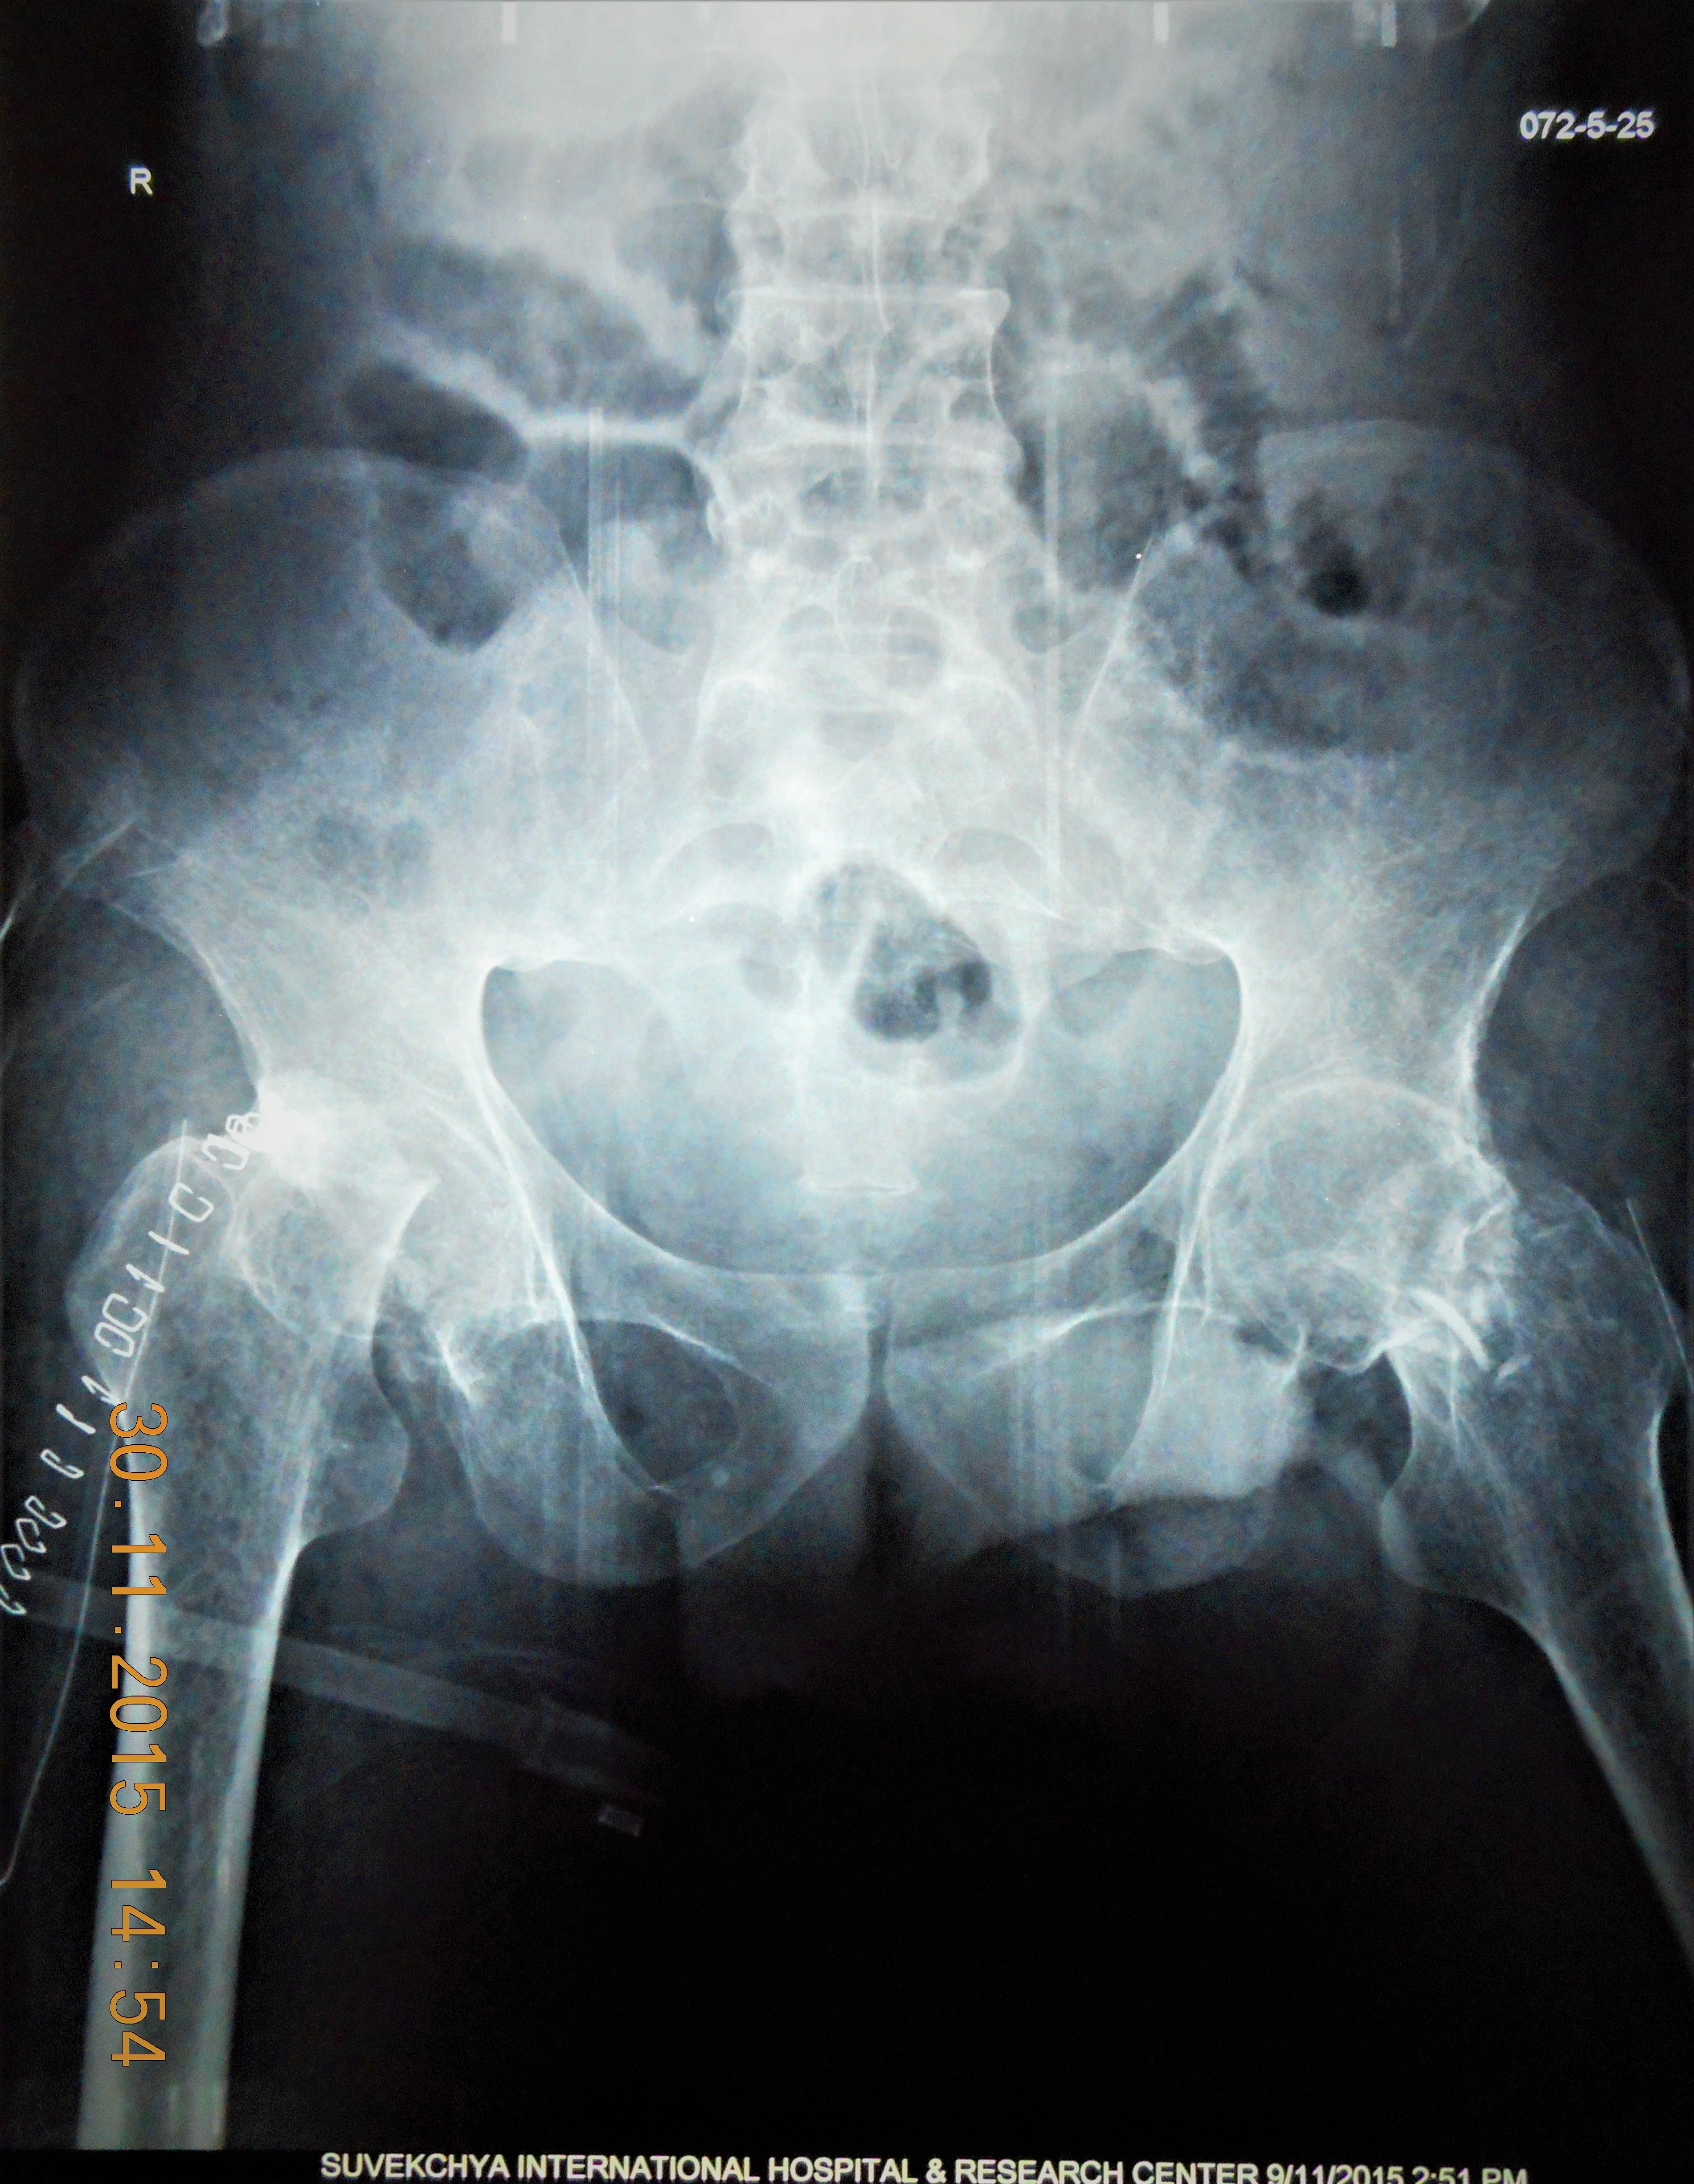

- 1 st Operation X Ray: BL Femoral Neck Osteotomy

- Post Op X Ray